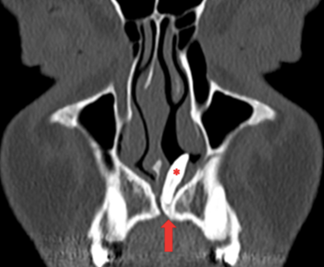

Răng thừa (b) mọc trong vòm miệng khiến cho R22 (a) mọc lệch xoay trục XQ răng toàn cảnh không thấy răng thừa do R21 (a) che khuất,(b) là R22 bị xoay trục

Hình ảnh răng thừa (a) xuất hiện rất rõ trên CT Cone Beam, (b) là hình ảnh R21

Hình 3: Tính ưu việt của CT Cone Beam trong chẩn đoán răng thừa

(Nguồn: Bệnh viện Đa khoa Tỉnh Quảng Trị)